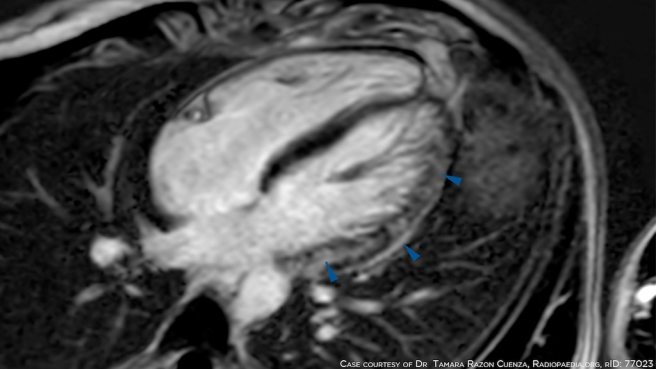

Case reports suggest a favorable clinical course after hospitalization

Fonte: First Close Look at Presumed Myocarditis Cases After COVID Vaccination | MedPage Today